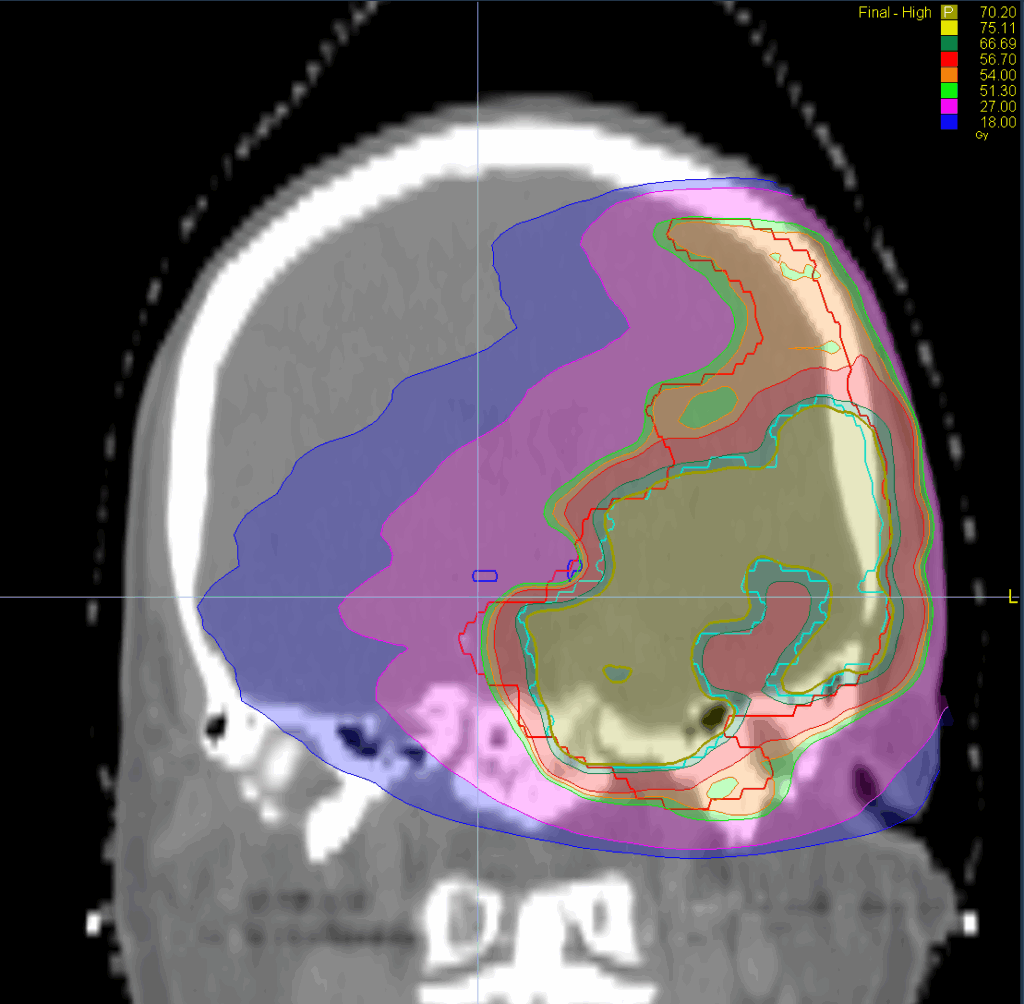

Treatment Plan Images

Fractionation / Protocol Used

70.20 Gy – 54Gy in 39 fractions

PTV(s) Volume, Length

280 cc, 12 cm

Mode

- TomoHelical™ 5 cm